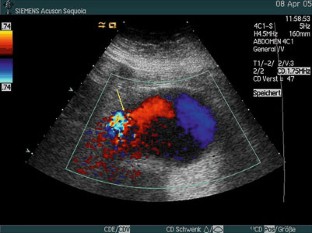

Fig. 7. A, B.